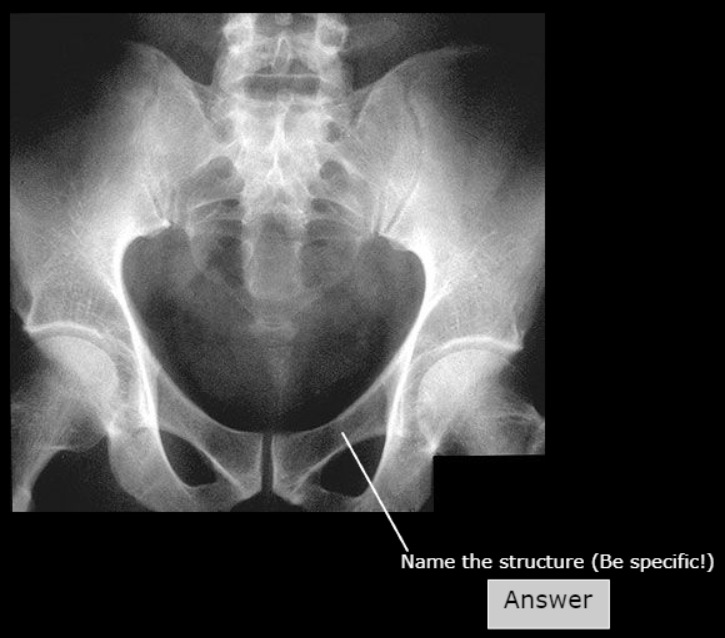

Pubic Symphysis